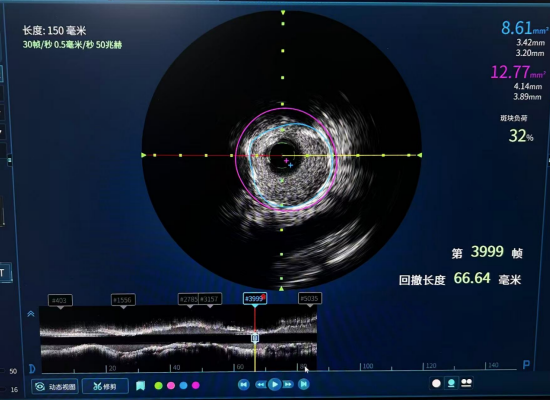

(IVUS术前)

(IVUS术后)

面对这一挑战,医院心血管专家团队决定启用血管内超声(IVUS)技术作为本次手术的“导航核心”。IVUS堪称介入医生的“第三只眼睛”,它能将一枚微型超声探头通过导管直接送入血管内部,从管腔内进行360度全方位扫描,生成高清的血管横断面图像。

·术前明察: IVUS首先精准评估了闭塞病变的“真面目”,明确了斑块的成分(是否为易破裂的软斑块或坚硬的钙化斑块),为选择最合适的介入器械提供了决定性依据。

·术中导航:在导丝通过最艰难的闭塞段时,IVUS实时成像如同“GPS定位”,帮助医生辨别真腔、规避夹层,确保了导丝始终行进在正确的路径上,极大地提升了安全性。

·术后优化:在球囊扩张并植入支架后,团队再次利用IVUS对结果进行了“质检”。通过评估支架的贴壁情况、扩张是否充分以及是否完全覆盖病变,确保了支架植入的“完美无瑕”,从根源上降低了术后再狭窄和血栓形成的风险。